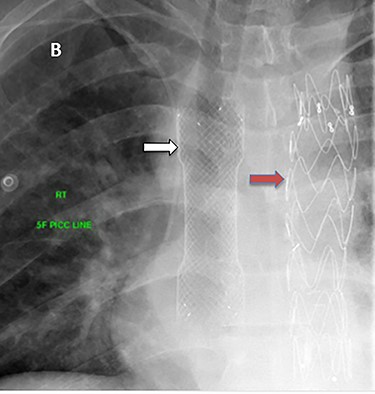

A 36-year-old male, involved in a minor motor vehicle accident while driving his car. He lost consciousness following a sudden onset of transient loss of vision which was not associated with palpitation or dizziness. His previous medical history revealed arterial hypertension and a corrected aortic coarctation with interposition graft at the age of 14. Pan CT scan was unremarkable except for thickening of the desending throacic aorta. His white blood count was very high (68 000 per cubic millimeter of blood). One day after the car accident, he developed nausea, hematemesis and melana. Upper GI endoscopy revealed blood in the stomach and distal esophafgus with no identifiable source of bleeding (Fig. 6). The patient developed massive hematemsis with hypotension requiring intubation and resuscitation. Another CT scan showed air pocket around distal aorta and contrast extravasation to the esophagus (Fig. 7). Another endoscopy revealed distal esophageal ulcer with clot extending toward the stomach (Fig. 8). AEF was suspected and then confirmed by aortogram. The fistula was treated by TEVAR (20 mm × 11.5 cm Valiant covered stent - Medtronic company, USA) followed by fully covered esophageal stent in the middle of the esophagus (Fig. 9).

(A) CT study with contrast showing gas adjacent to the descending thoracic aorta with thickened soft tissue around the esophagus. (B) Vascular contrast within the esophagus and projecting outside the aorta forming ‘pseudoaneurysm’ or penetrating aortic ulcer.